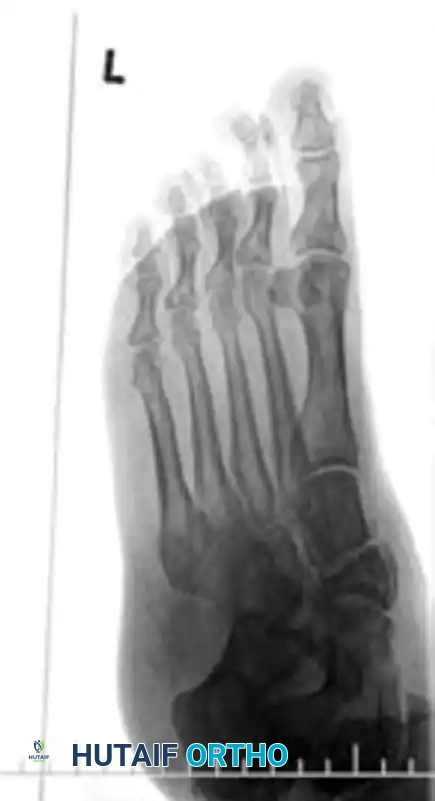

1. The medial shaft of the 2nd metatarsal must align perfectly with the medial aspect of the middle cuneiform on the AP view.

2. The medial shaft of the 4th metatarsal must align perfectly with the medial aspect of the cuboid on the oblique view.

3. The 1st metatarsal-cuneiform articulation must show no incongruency.

4. The "Fleck Sign": Look for a small bony avulsion in the space between the medial cuneiform and the base of the 2nd metatarsal. This represents a bony avulsion of the Lisfranc ligament.

5. Evaluate the naviculocuneiform articulation for subtle subluxation.